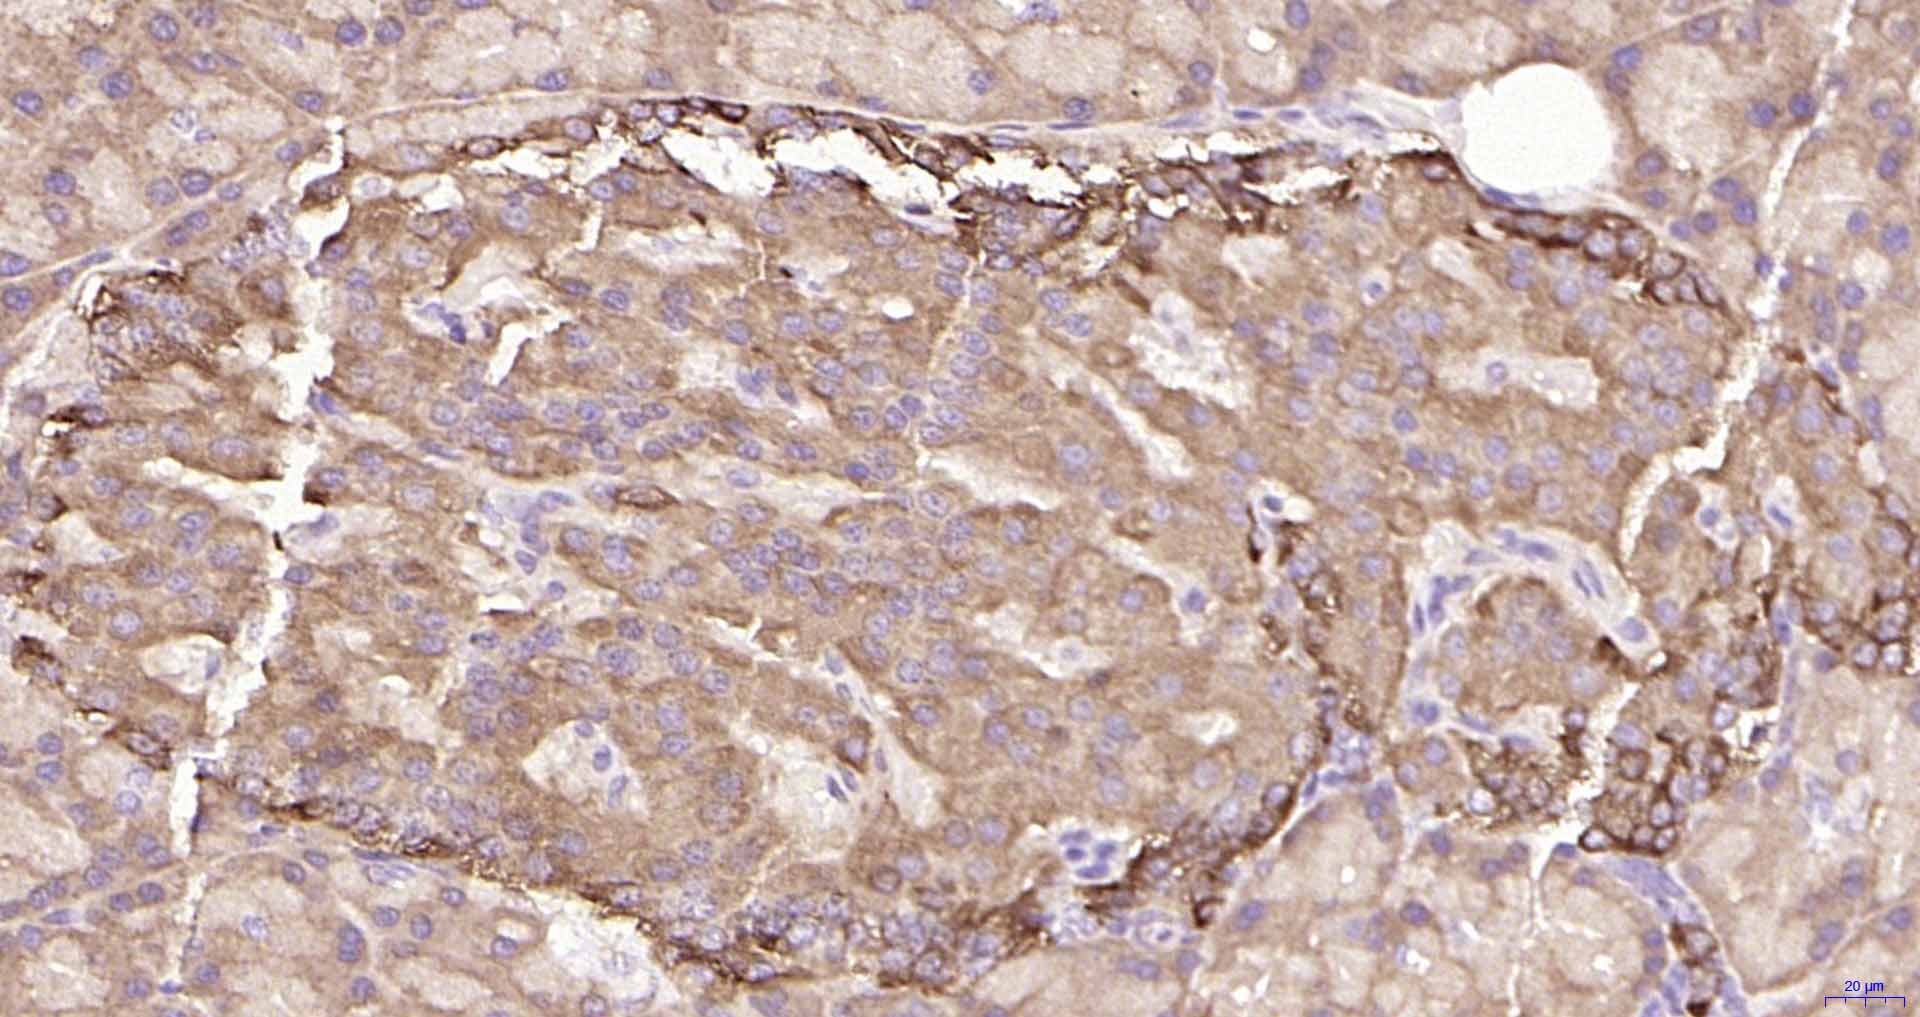

Paraformaldehyde-fixed, paraffin embedded Rat Pancreas; Antigen retrieval by boiling in sodium citrate buffer (pH6.0) for 15 min; Antibody incubation with ULK1 Monoclonal Antibody, Unconjugated(bsm-61039R) at 1:100 overnight at 4°C, followed by conjugation to the SP Kit(Rabbit, SP-0023) and DAB (C-0010) staining.